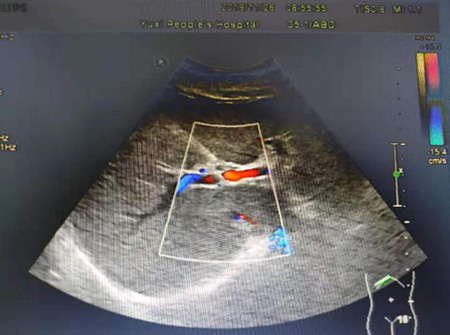

D超是多普勒(Doppler)调制超声诊断的简称,也叫彩超,是利用多普勒原理变将血流信号换成容易识别的彩色信号,二维超声加上血流图就形成了大家所说的彩超。

彩超主要用于心脏病检查和人体各脏器内外的主要血管的血流检测。如在诊断消化系统、泌尿系统疾病中,通过彩超获取门静脉、肝动脉、肾动脉的血流信息。除此之外彩超还重点用于心脏及瓣膜疾病的诊断,是先天性心脏病的重要诊断手段,并且在诊断心功能,心瓣膜疾病(二尖瓣狭窄,二尖瓣关闭不全,心肌病等)发挥重要作用。

正常肝脏彩超声像图